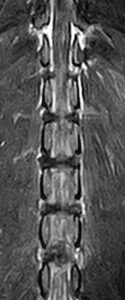

フレブルちゃん両後肢麻痺グレード5でMRI検査及び手術依頼でご紹介がありました。MRI検査で第4-5腰椎間椎間椎間板ヘルニア、右側優位な圧迫と診断し即日手術となりました。→<その2>へ続く